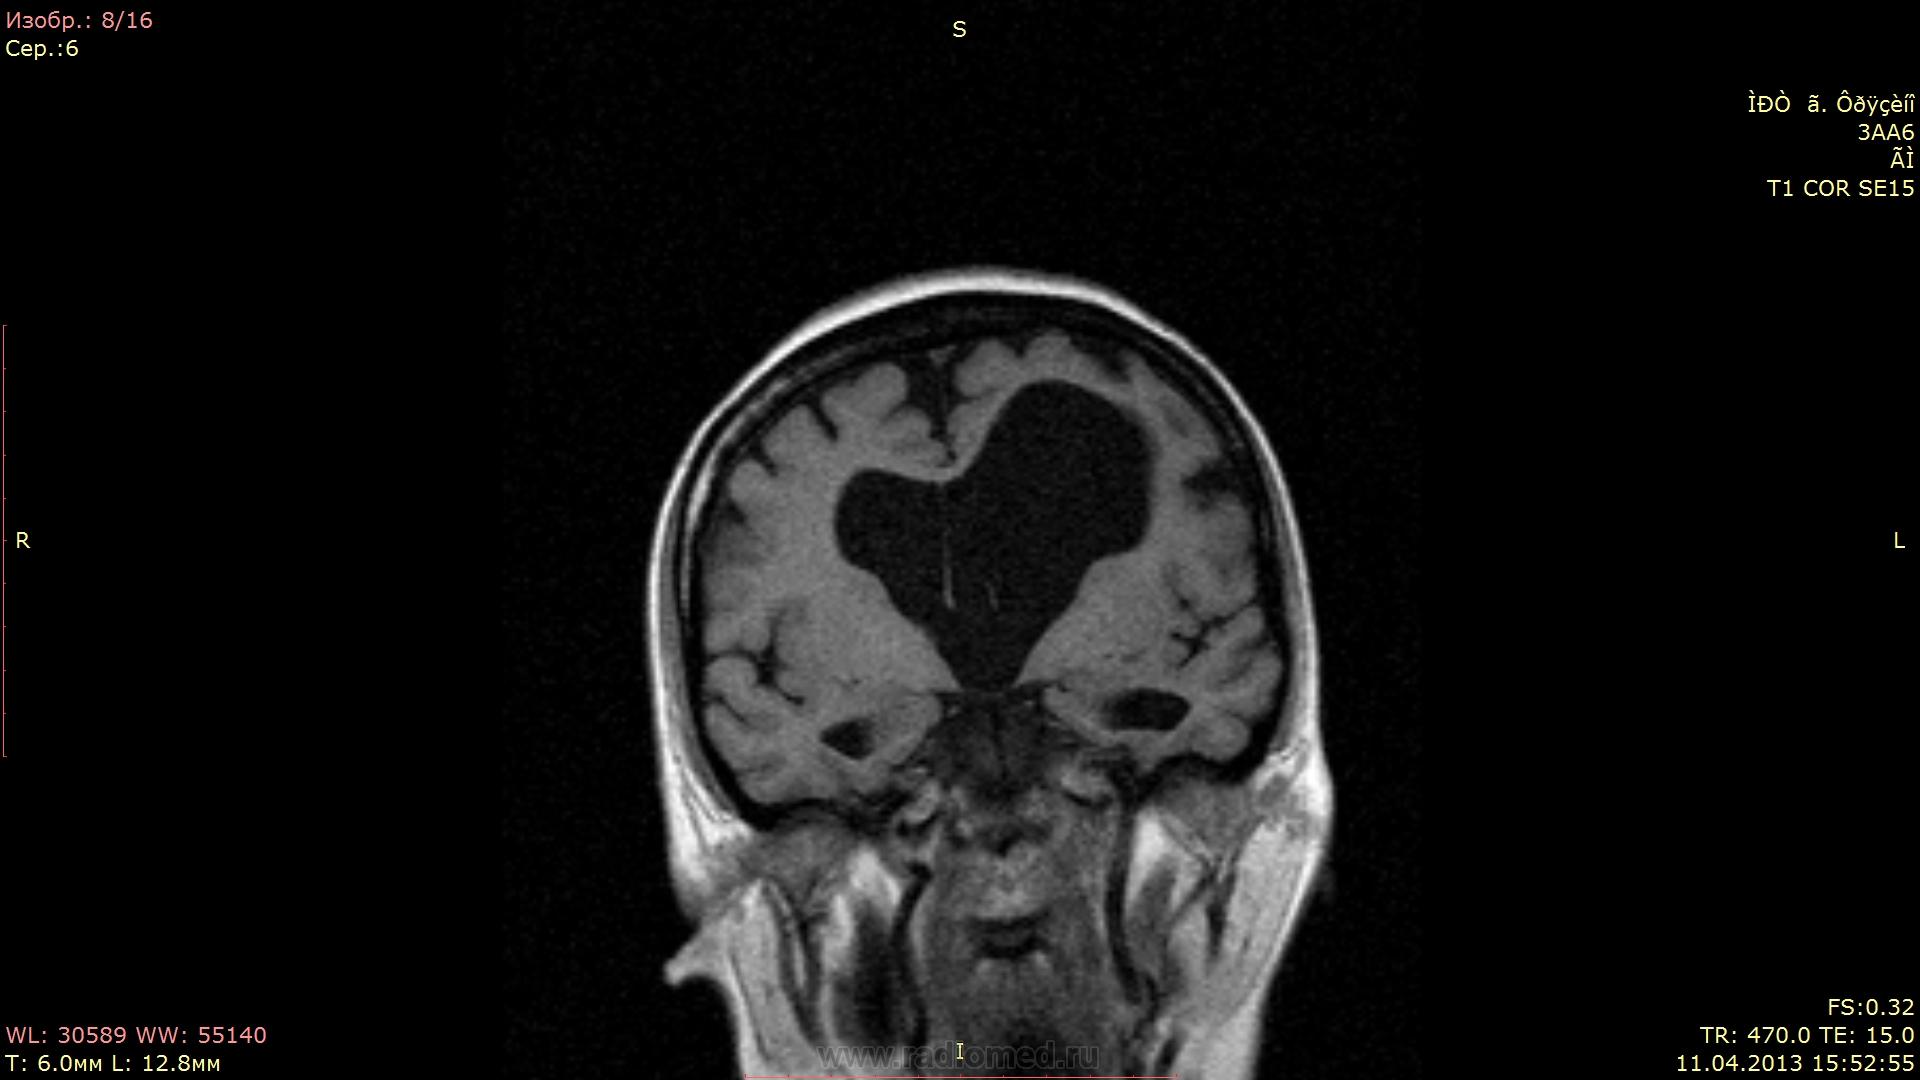

Женщина 53 года... Не могу найти причину гидроцефалии...

Окклюзия на уровне сильвиева водопровода. А причина...?

Не вижу окклюзии на уровне Сильвиева водопровода. Внутренняя неокклюзионная гидроцефалия.

А вообще-то, от рентгенолога требуется указать на наличие или отсутствие явных признаков повышения внутрижелудочкового давления (перивентрикулярный отек), а в случае наличия такового - выявить уровень и причину окклюзии. Здесь открытая, преимущественно внутренняя гидроцефалия, т.е. окклюзии нет, давление в желудочках условно считается  нормальным, и вмешательства нейрохирурга не требует.

А если рассуждать о причинах - то это, скорее всего, перинатальное гипоксически-ишемическое или травматическое поражение, приводящее к затруднению резорбции ликвора в подпаутинных пространствах. Пациентка живет с этой гидроцефалией всю жизнь.

Там еще и киста прозрачной перегородки, кстати! Не могу подтвердить это литературой, но по моим собственным наблюдениям, у недоношенных детей или у детей с перинатальными проблемами листки прозрачной перегородки часто остаются несращенными.

Давление в желудочках "условно нормальное", но дно третьего желудочка пролабирует в селлярную область:)

Про сочетание вышеописанных признаков достоверно сказать не чего не могу, известно что неврологические проблемы около 2-х лет. В данном случае меня смутила ассиметрия боковых желудочков и пролабирование третьего желудочка, нормальный четвертый желудочек... В общем стаж мой в МРТ очень маленький и я боялся пропустить оклюзию на уровне водопровода.